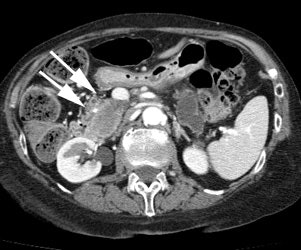

Pancreatic cancer: The patient shown below had a history of thyroid cancer and was being evaluated for a large neck mass. The PET scan revealed intense uptake in the abdomen anterior to the right kidney (black arrows). Subsequent CT imaging revealed a large mass in the pancreatic head (white arrows). There is atrophy of the remainder of the pancreas and dilatation of the pancreatic duct. |

|